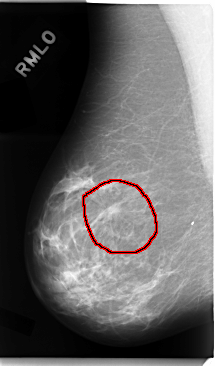

C_0034_1.RIGHT_MLO

FILE: C_0034_1.RIGHT_MLO.OVERLAY

TOTAL_ABNORMALITIES 1

ABNORMALITY 1

LESION_TYPE MASS SHAPE IRREGULAR MARGINS SPICULATED

ASSESSMENT 5

SUBTLETY 5

PATHOLOGY MALIGNANT

TOTAL_OUTLINES 1

BOUNDARY